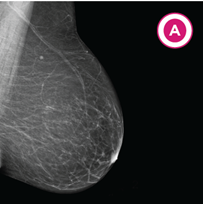

A. Almost all fatty: